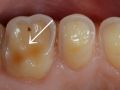

歯の表面を覆うエナメル質はph5.5以下になると溶け始めます。

そうすると、冷たい飲食物が凍みる知覚過敏やむし歯のような痛みが起こります。また、歯の表面が白濁(はくだく:白く濁ること)したり、黄ばむこともあります。